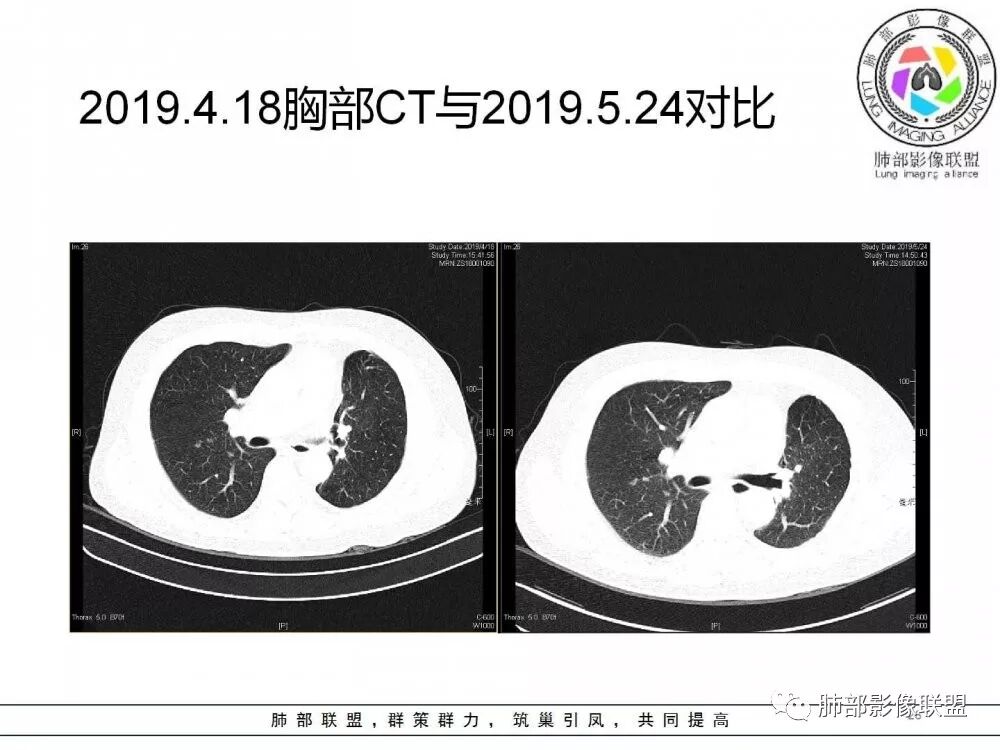

肺部病灶从2月份就开始有了,应该最早说是1月7号就有了,到3月13号稍微增大一点,到后面几乎就没变化了,到5月份好像稍微大一些,炎性肯定是炎性,就是这个炎性是到底什么病变呢?其实本没变化,它特点一个是在叶裂上,跟血管关系密切,但是病灶边缘稍收缩,病灶这么没有太大变化,我还是支持炎性病变。

确实当时病人来了考虑转移可能,就测了基因,上了靶向药,两月变化不大

因为这个长轴似乎跟支气管走行一致的,其实治疗效果不是很理想,我先把性质定为炎性。因为这个病灶它沿着血管支气管走行的方向,大家都考虑隐球菌,这么久病灶无明显变化,它跟血管束关系很密切。我犹豫就在此,到底是IgG4还是隐球,大方向是炎性,不符合的就是也在激素治疗。

19年3月份才吃靶向药